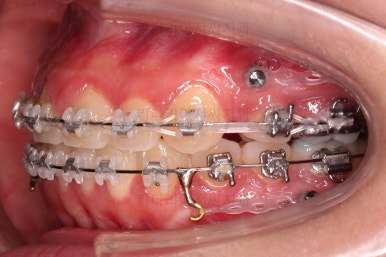

부산치아교정 이번 치료의 핵심인데요.

결손 부위에 미니스크류를 이용해서 뒤쪽 어금니들을 결손 부위로 앞으로 앞으로 계속 당겨줍니다.

얼굴모습에서의 중앙선도 지속저으로 체크하면서 한 쪽으로 치우침 없이 마무리를 해야 하고요.

틈새가 줄어들 때 까지 같은 작업을 반복합니다.

점점 틈새가 붙어가는게 보이죠?

계속 반복합니다.

틈새는 거의 다 붙어가는데 교합이나 중앙선 등을 위해 추가적으로 밀고 당기기를 해줍니다.

디테일을 좀 더 맞추고 부산치아교정 마무리를 합니다.

치아 갯수 및 사이즈 문제로 위아래의 정중선은 100% 일치시키긴 힘들지만 가능한 선에서 최대한 맞추었고요.

윗니가 1개 없는 상태에서의 교합도 잘 맞추고 마무리를 했습니다.